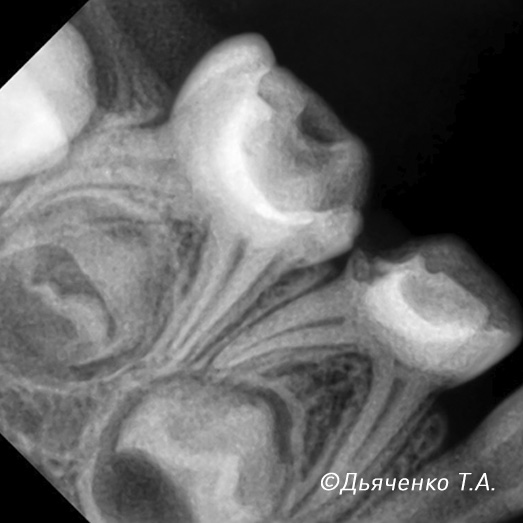

При обширном воспалении нерва, когда воспаление необратимо, может потребоваться его полное удаление с очисткой и пломбированием каналов (рис. 2 и 3).